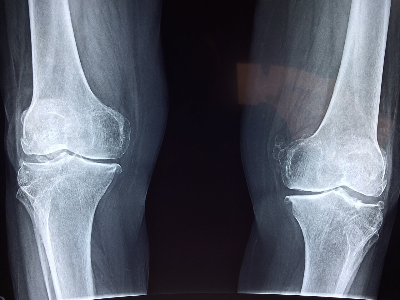

1. 골밀도 검사

이중 에너지 X-선 흡수계측법은 골밀도를 측정하는 데 가장 일반적으로 사용되는 검사입니다.

이 검사는 건강한 젊은 성인의 골밀도와 비교하여 T-점수를 제공합니다.

T-점수가 -1 이상이면 정상으로 간주되며, -1~-2.5는 골감소증(낮은 골밀도), -2.5 이하는 골다공증을 나타냅니다.